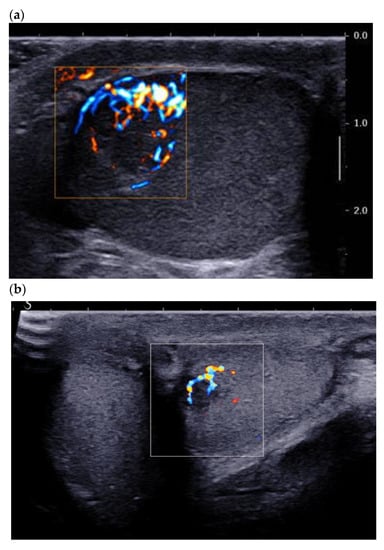

3.2. Color Doppler and Ultrasensitive Doppler